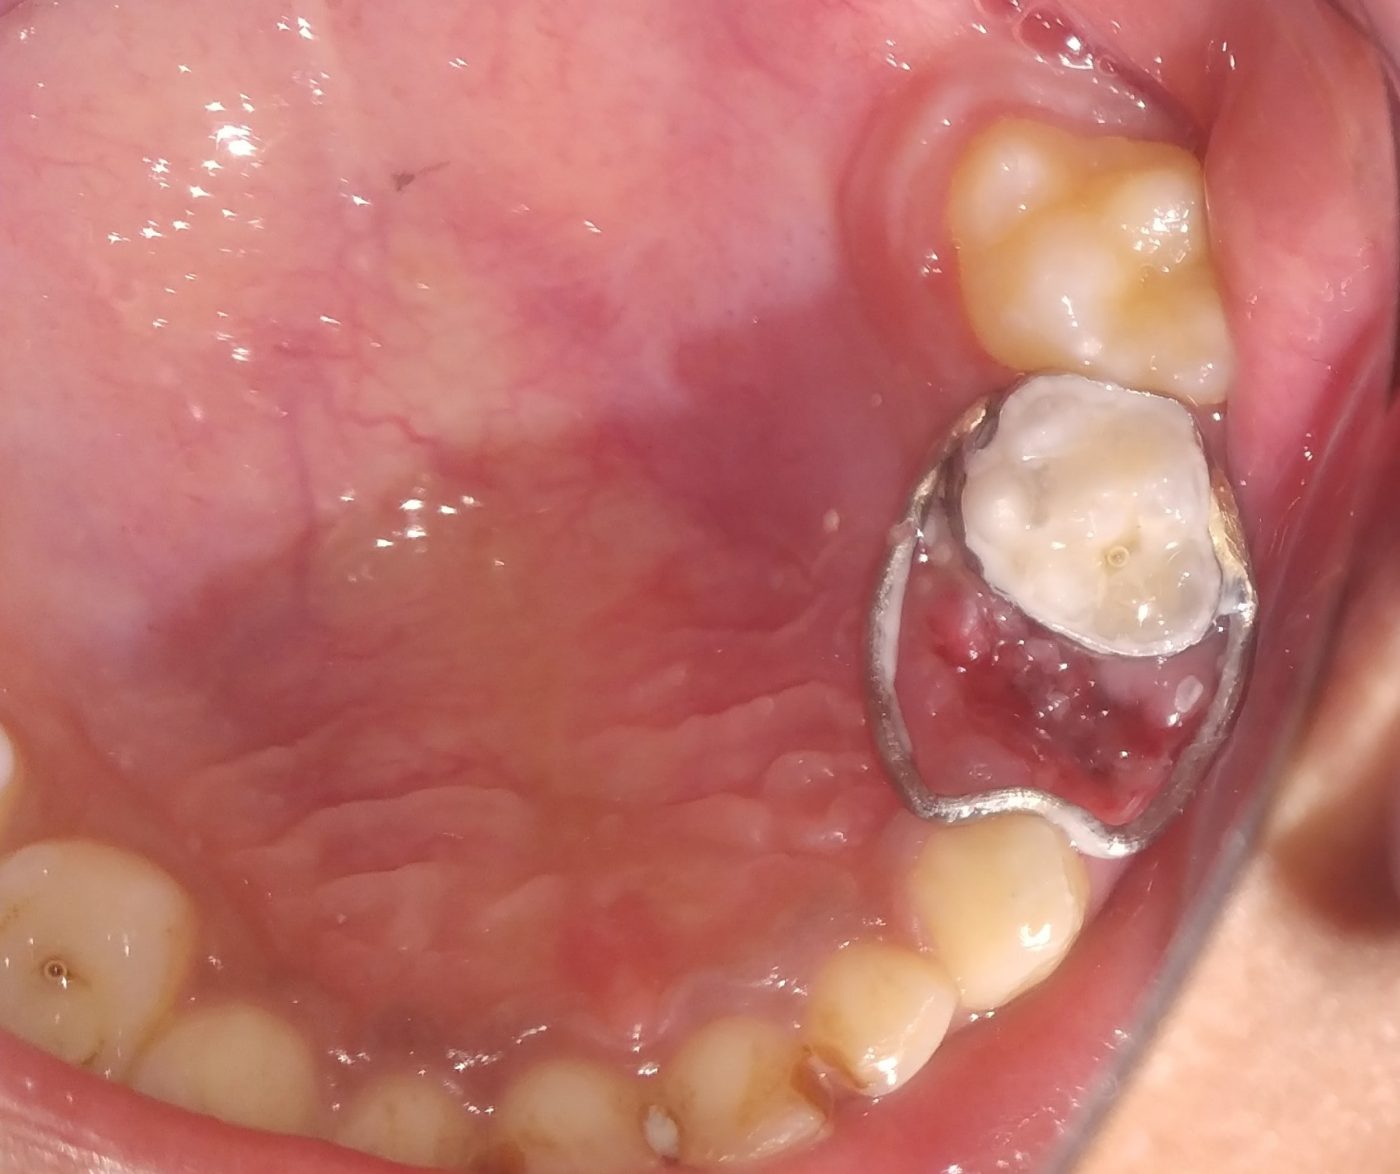

Treatment and Services